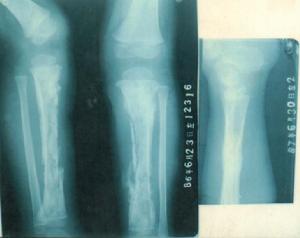

創傷後骨髓炎常見患者部位診斷依據:1.開放骨折和骨折手術固定後出現:高熱、紅腫、疼痛。2.X線片顯示:碎骨片壞死、暴露骨端壞死。

創傷後骨髓炎骨質透視(1)急性期立即敞開創口引流,以免膿液迸入骨髓腔內。